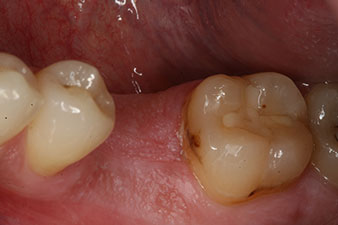

композитна корона

Фиг. 9: Окончателната композитна корона е циментирана върху хибриден PEEK абатмънт в лабораторията и може веднага да се завие на място.